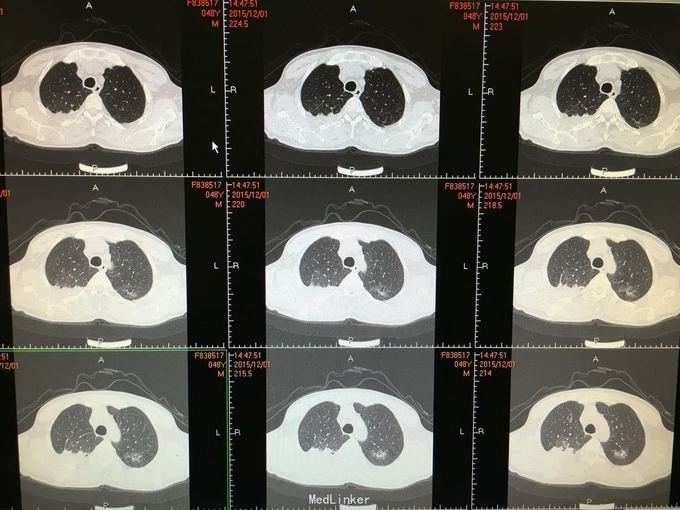

间断咳嗽咳痰5月余。患者缘于半年前确诊为骨髓增生异常综合征,并行造血干细胞移植术。术后出现发热,完善相关检查考虑为肺部真菌感染,给予抗感染治疗后体温正常,病情好转出院。出院后仍有间断咳嗽咳痰,咳黄色痰,无发热,自行口服伏立康唑200mg,2/日治疗,12月初复查CT提示双肺病灶较前进展,右肺中叶新增病灶。

根据症状体征及辅助检查,结合病史考虑真菌感染可能性大。进一步气管镜检查,结果如下。组织活检标本可见。病理回报提示真菌团,培养见曲霉菌生长。明确诊断后给予两性霉素B雾化吸入及伏立康唑静脉应用抗真菌治疗,同时给予环孢素口服。

造血干细胞移植后肺部感染常见,其中以曲霉、卡肺等多见,患者经气管镜检查已将真菌团块取出。术后给予监护,口服云南白药、垂体后叶素雾化止血等治疗,无明显出血,症状逐渐好转。复查CT也明显好转。